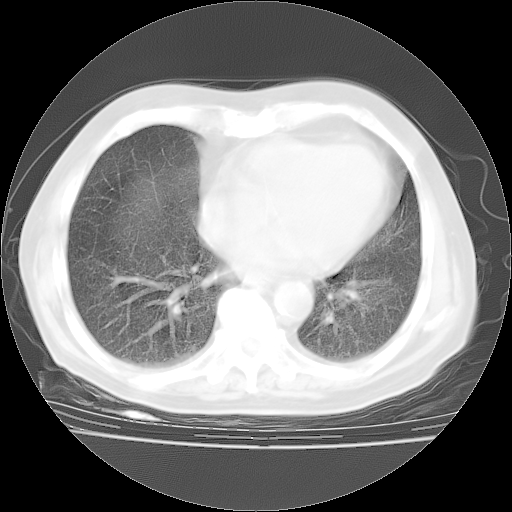

今天部分检查

轻微咳嗽,无痰,(体温正常时)R20次/分,P75次/分,双肺底、腋下可闻及少量捻发音。下肢轻度浮肿。

血常规:白细胞9.11×109/L,N0.92,L5.64,血小板39.2×109/L,HB148g/L,ESR2mm/H。

尿常规:潜血+

血生化:总蛋白69.71g/L,白蛋白38.40g/L,球蛋白31.31g/L,CRP27.9mg/L,尿素氮11.98mmol/L,肌酐106μmol/L,乳酸脱氢酶1099 U/L,肌酸激酶108U/L,CK-MB 61U/L。

腹部B超:胆囊壁增厚,肝、胆、胰、脾、肾无异常,肠系膜淋巴结、腹膜后淋巴结无增大。

ECG:右心室增大

心脏超声检查:无右心室增大。

增加治疗:异烟肼、利福平、乙胺丁醇,静滴左氧氟沙星、参麦注射液。甲强龙从80mg暂减为40mg。

强的松3月1日改为10mg qd,4月1日改为10mg qod。3月份以前的减量过程和环磷酰胺疗程需等明天查看记录(我岳父自己做的记录在他家里)。